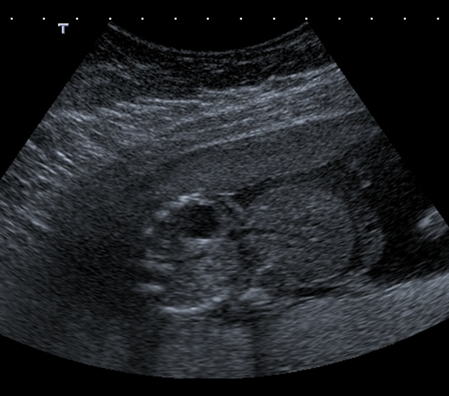

This axial scan through the fetal abdomen might lead you to believe that there are two babies lying side by side.